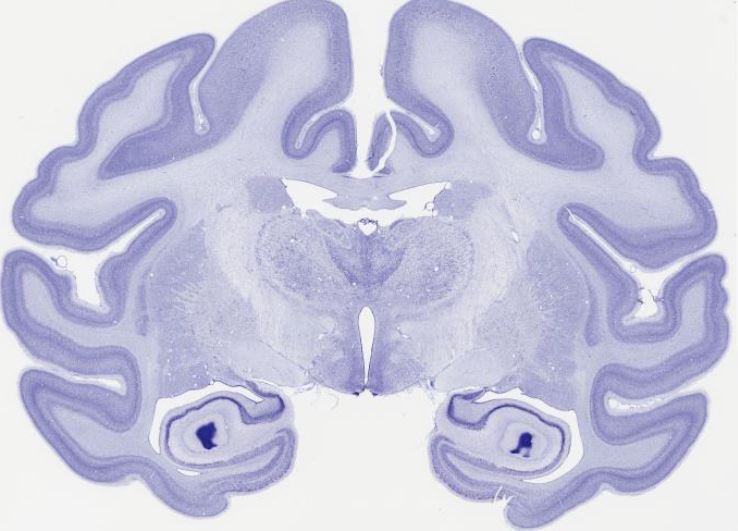

brain